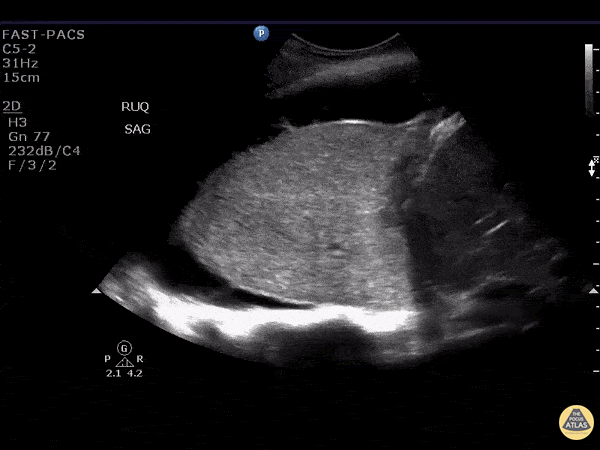

This is an image demonstrating dense lung consolidation with surrounding pleural effusion. Patient ultimately was diagnosed with bronchogenic CA with complete bronchial obstruction. Image courtesy of Robert Jones DO, FACEP @RJonesSonoEM Director, Emergency Ultrasound; MetroHealth Medical Center; Professor, Case Western Reserve Medical School, Cleveland, OH View his original post here